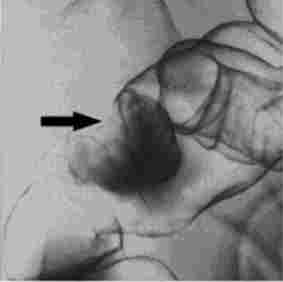

Мал. 14.1. Іригоскопія.

Дефект наповнення при поліпи товстої кишки

Залежно від клінічної ситуації підготовка може бути проведена або шляхом прийому проносних, або очисними клізмами. Пацієнтам, які страждають запорами, рекомендується за 2-3 діб до процедури перейти на бесшлаковую дієту. При проведенні рентгенологічного дослідження (іррігоско- ПІІ) використовують методики тугого і напів тугого заповнення кишечника контрастом; також застосовують метод подвійного контрастування - роздування повітрям заповненої контрастом кишки. Як контрастної речовини використовується сульфат барію. Рентгенологічні ознаки поліпів кишечника - наявність чітких округлих дефектів наповнення (рис. 14.1).

Дане дослідження дозволяє виявити поліпи діаметром до 3-4 мм. При малігнізації новоутворень з'являються ознаки «із'еденно- сти» контурів, можливо наявність стійкого барієвого депо, ригідність і втягнути стінки кишки.